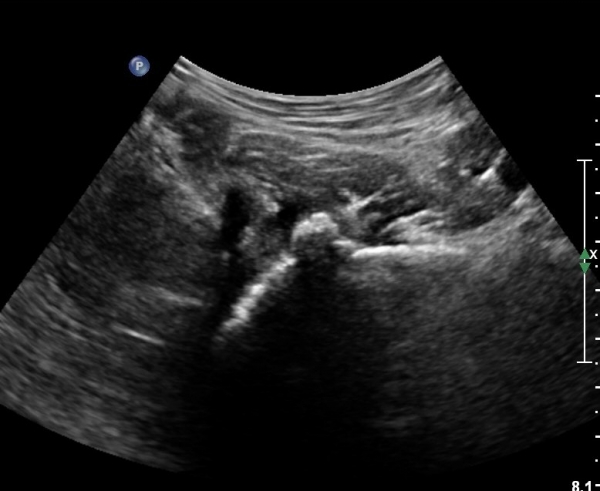

[¾ûµ¢ÀÌ] ¾ûµ¢ÀÌ °üÀý¼ø ÆÄ¿­ÀÇ ÃÊÀ½ÆÄ°Ë»ç(ultrasonography of labrum tear of hip joint)

ÃÊÀ½ÆÄ °Ë»ç

Sonography of the Acetabular Labrum Visualization of Labral Injuries During Intra-Articular Injections

What is the role of clinical tests and ultrasound in acetabular labral tear diagnostics?

Sonographic evaluation of anterosuperior hip labral tears with magnetic resonance arthrographic and surgical correlation.